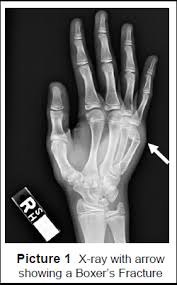

Conditions And Treatments

Conditions And Treatments from www.eorthopod.com